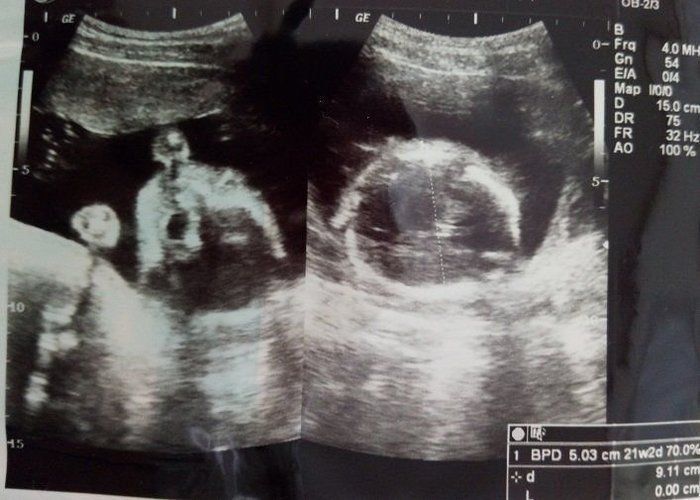

たかこさんの妊娠20週目のエコー写真 ちょっとホラー並みのエコー写真でコンニチワ

エコー写真ではいつも背中を向けていた胎児が、ついにこっちを向きました。すると、ちょっとしたホラーのような写真に…。写真下の絵は、先生の手書きの説明です。この頃になると、全長を測るのではなく、大腿骨長(太ももの骨の長さ)を測り、大きさの目安にすると先生に説明されました。この時に男の子のシンボルがしっかり映り、性別もほぼ確定しました。つわりもようやくなくなりました。